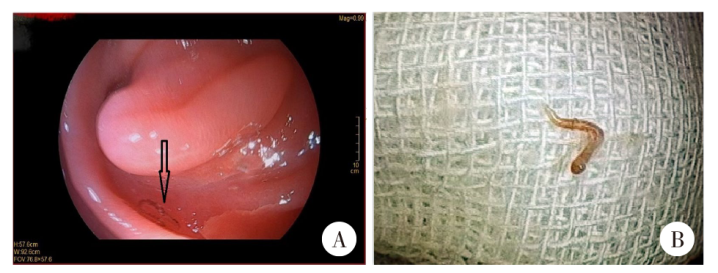

患者,男,72岁,河南南阳人,常住深圳市,有以蚯蚓为诱饵钓鱼的习惯。2023年因胃癌接受胃切除术,在例行电子胃镜复查时发现空肠部位有线虫寄生,但是无典型呼吸道及消化系统临床表现。血常规检查显示,白细胞数为6.61 × 109/L,嗜酸粒细胞百分比为0.7%,嗜酸粒细胞绝对值为0.05 × 109/L,各项指标均在正常范围内。以活检钳取出虫体。虫体呈红色,细长且呈不典型“Y”字型,长度约10 mm,可自主活动。虫体经哈瑞氏苏木素染液处理,在光学显微镜下鉴定为兽比翼线虫(Mammomonogamus)雄虫。患者被诊断为兽比翼线虫感染,采用口服阿苯达唑(400 mg/d,每日1次,疗程为1周)治疗。治疗后1周,患者粪便中未检测到兽比翼线虫虫卵。

The patient was a 72-year-old male from Nanyang, Henan Province, with a permanent residence in Shenzhen City, who had a habit of fishing using earthworms as baits. He underwent a gastrectomy for gastric cancer in 2023, and nematodes were found parasitizing the jejunum during a routine electronic gastroscopic follow-up; however, but no typical clinical manifestations of respiratory or digestive system were observed. Routine blood tests showed a white blood cell count of 6.61 × 10⁹/L, an eosinophil percentage of 0.7%, and an absolute eosinophil count of 0.05 × 10⁹/L, with all indicators within the normal range. The nematodes were removed using biopsy forceps, appearing red, slender, and atypical in shape with a “Y” configuration, measuring approximately 10 mm in length and capable of autonomous movement. Following staining with Harris’s hematoxylin, the nematodes were identified as male Mammomonogamus under an optical microscope. The patient was diagnosed with Mammomonogamus infection and orally administered with albendazole (400 mg/d, once daily for one week). No Mammomonogamus eggs were detected in the patient’s stool samples one week post-treatment.